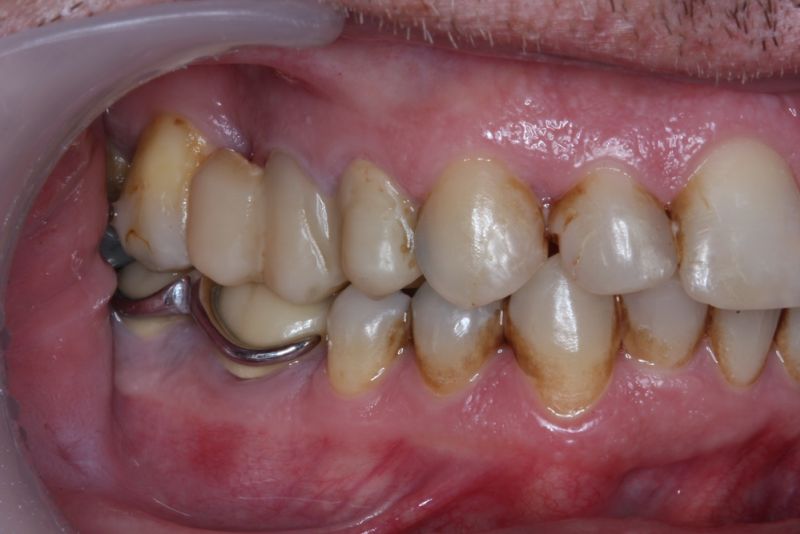

Der Patient hat von einem CMD Spezialisten in Bielefeld einen Aufbissbehelf erhalten. Den hat der Patient mit Zellstoff unterfüttert, weil der Aufbissbehelf so unterschiedlich hoch war, dass der Patient es vor Schmerzen mit dem Aufbissbehelf nicht ausgehalten hat.

Erkennbar ist die massive Abweichung der habituellen Bisslage von der neuromuskulär zentrierten Bisslage.